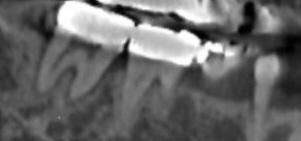

어금니 치료방법 알수잇을까요.,,?

치료방법이알고싶습니다. 염증소견잇다고들엇고

흔들리기는하지만 아프지도 식사하는데문제가없습니다

엑스레이입니다